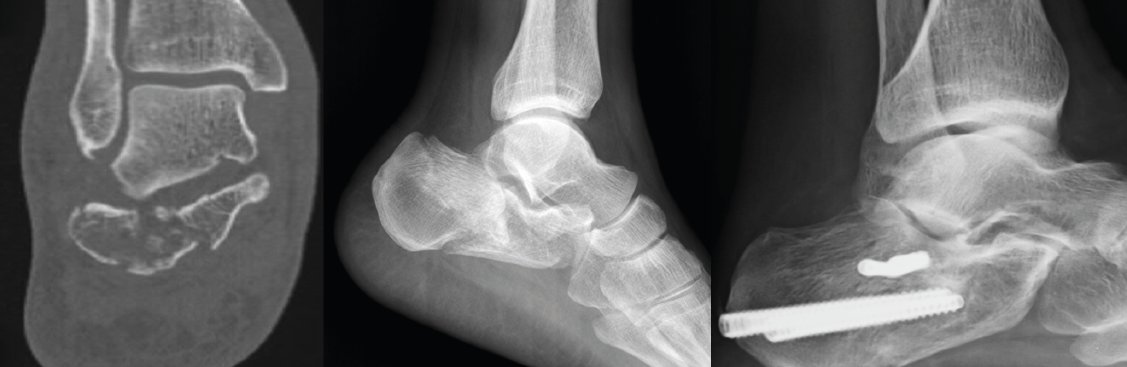

Figura 3. Varón de 59 años con fractura del calcáneo de Sanders de tipo IIA tras caída de 2 m de altura. Ángulo de Böhler precirugía de 6,3°, ángulo de Böhler poscirugía de 20,7° y a los 3 meses de 22,3°. No presentó ninguna complicación.

Cuando tenemos todos los fragmentos en su posición anatómica, habiéndose conseguido la reducción de la superficie subastragalina posterior, se fijan de manera provisional dichos fragmentos con agujas de Kirschner (aK) de 1,0 o 1,2. Estas aK fijan los fragmentos laterales de la fractura a la zona medial que normalmente está intacta. Se comprueba bajo fluoroscopio (proyección lateral) que se ha restablecido el ángulo de Böhler (Figura 3) y se fija de forma definitiva con 2 o 3 tornillos canulados de lateral a medial.

Figura 5. Varón de 37 años con fractura del calcáneo de Sanders de tipo IIB tras caída de altura. En la imagen de la tomografía computarizada se observa hundimiento de la zona lateral de la subastragalina posterior y un trazo posterior “en lengua”. Ángulo de Böhler precirugía de 8,5°.

A la hora de corregir el varo-valgo y la longitud del calcáneo colocamos un pin Steinmann o aK de 3,0 o 4,0 en la tuberosidad posterior y damos angulación varo o valgo (Figura 4) según necesite cada caso y siempre comprobando con la fluoroscopia (proyección axial). Una vez conseguida la angulación correcta, se fija de forma definitiva con 2 tornillos canulados de posterior a anterior (Figuras 5 y 6).

Figura 6. Se fijó con 2 tornillos canulados de lateral a medial, 2 tornillos de posterior a anterior y 1 tornillo cerrando el trazo en lengua. Ángulo de Böhler poscirugía de 30,9° y a los 3 meses de 32°. No presentó ninguna complicación.